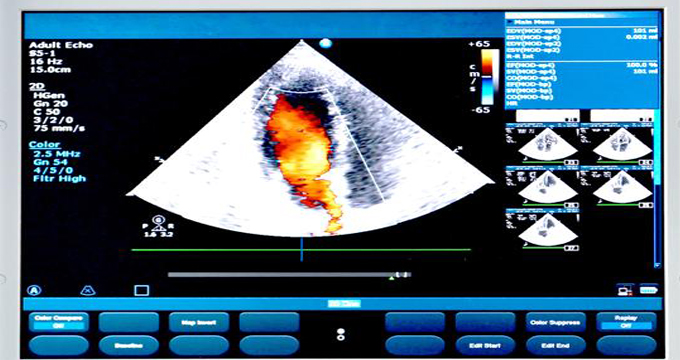

Davide Astori aveva 31 anni, era capitano della Fiorentina ed è morto improvvisamente in una camera di albergo. Le prime informazioni parlano di arresto cardiocircolatorio, ma come è possibile che uno sportivo così giovane sia deceduto in questo modo, senza una ragione? “È fondamentale che in un caso come questo venga eseguita l’autopsia e vengano prelevati i campioni di sangue per effettuare le prove genetiche”, spiega la professoressa Silvia Priori, professore ordinario di Cardiologia dell’Università di Pavia e Direttore Scientifico degli Istituti Clinici Scientifici Maugeri. “Spesso infatti le malattie genetiche, possono sfuggire alla diagnosi anche quando vengono eseguite visite accurate e tutti gli esami indicati. Questo accade perché queste malattie anche quando sono in una forma iniziale in cui il danno del muscolo o della trasmissione dell’impulso elettrico sono invisibili all’ecocardiografia o all’elettrocardiogramma, possono già causare arresto cardiaco fatale come prima manifestazione”.